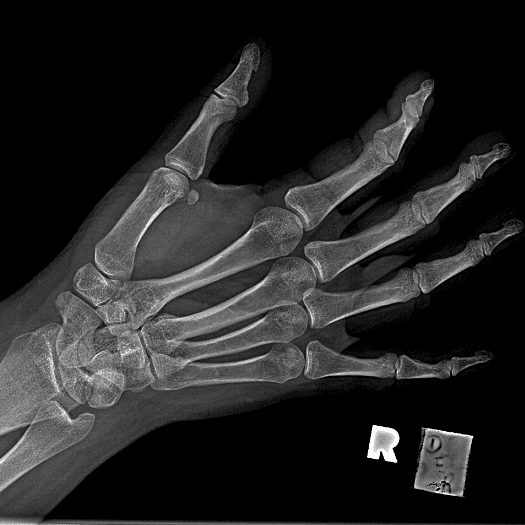

Simuliert den Dienst durch subtile oder schwierige Fälle und einige Normalbefunde.

30 Fälle